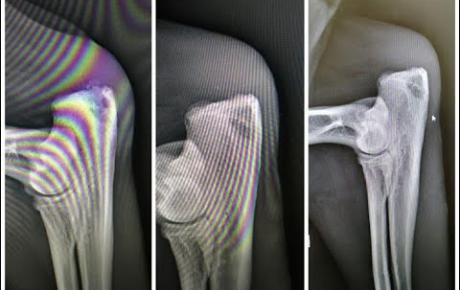

MLS Laser Therapy is included in the treatment plan of an 8-year-old sheepdog with acute relapse of bilateral stifle arthritis.